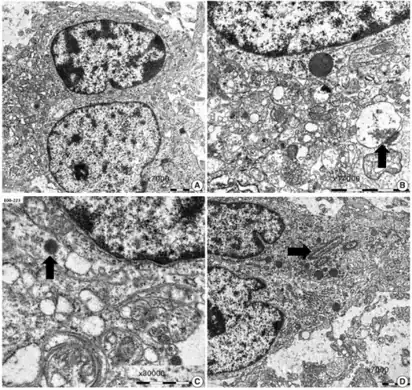

Dysembryoplastic neuroepithelial tumours are largely glioneuronal tumours, meaning they are composed of both glial cells and neurons.[2]

There currently exists some debate over where to make the proper division for the subunits of DNTs. A fourth subunit is sometimes noted as a mixed subunit. This mixed subunit expresses the glial nodules and components of ganglioglioma.[1] Other findings suggest that DNTs require a reclassification to associate them with oligodendrogliomas, tumours that arise from solely glial cells.[3] These reports suggest that the neurons found within DNTs are much rarer than previously reported. For the neurons that are seen in the tumours, it is suggested that they had been trapped within the tumor upon formation, and are not a part of the tumour itself.[3]